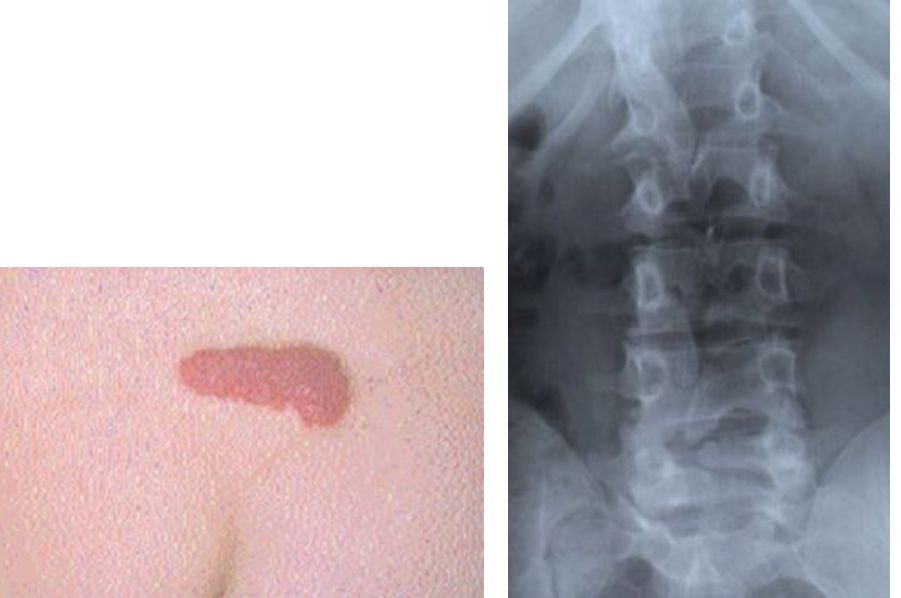

Las lesiones en la piel que  se encuentran sobre la columna vertebral, tales como lipomas y parches de pelos, son bien reconocidas como marcadores de anormalidades subyacentes ocultas, conocidos como disrafismo espinal oculto.

Las lesiones de piel sobre la columna, especialmente la región lumbo-sacra, que han sido consideradas como marcadores de disrafismo espinal, incluyen  lipomas, hoyuelos, parches de pelo, lesiones fibrosas como cicatrices, apéndices cutáneos, y colas vestigiales, lesiones vasculares, incluyendo hemangiomas, manchas de vino oporto y los senos dérmicos.

Lesiones hiperpigmentadas también han sido consideradas asociadas a estos desordenes. Aunque las manchas mongólicas azules o negras no son patológicas y no se asocian con disrafismo.